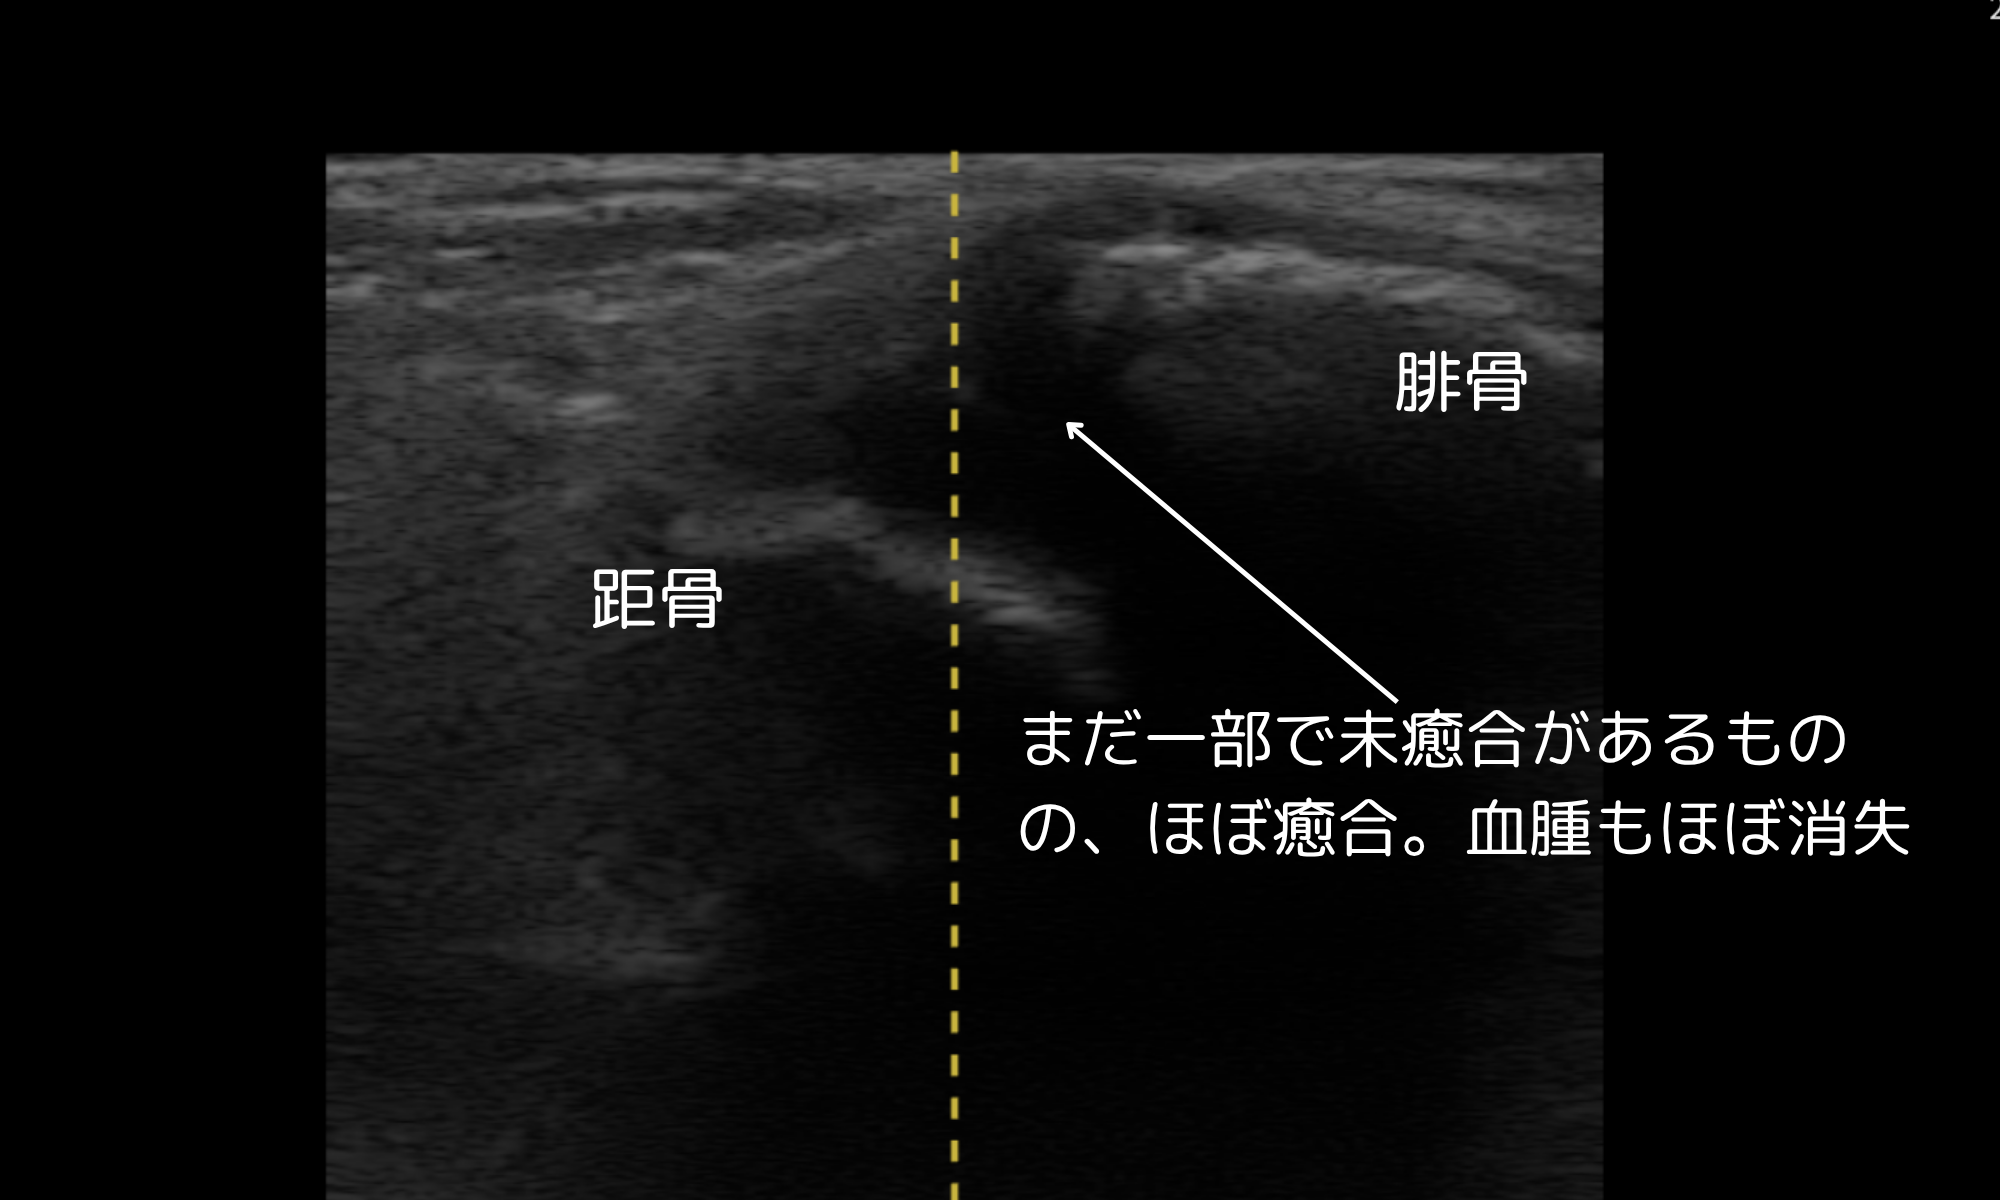

10月17日(受傷約3週間)

- 血腫縮小、骨片の癒合進行をエコーで確認

- 腫脹・圧痛ともに消失 → 医師より全荷重(FWB)許可、固定解除

- 軽量サポーター装着、ROM訓練開始